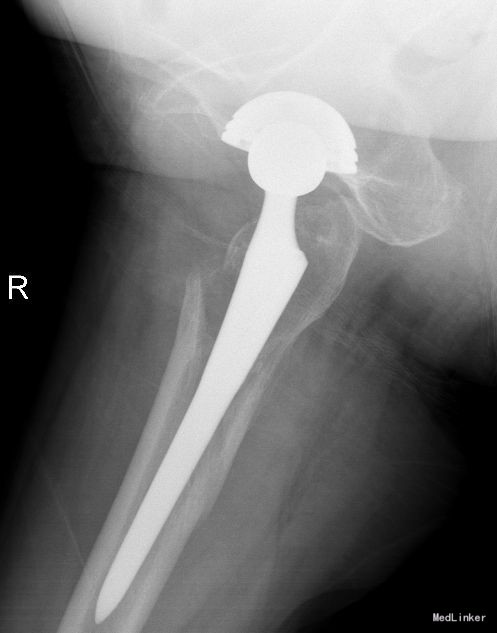

望:神志清,精神尚可,面色红润,营养良好,体型中等,舌红,苔薄黄;闻:语声清晰,呼吸均匀,未闻及特殊气味;切:脉弦紧。平车推入病房。右下肢较对侧未见明显短缩,外旋畸形,肌肉未见明显萎缩,右腹股沟饱满,腹股沟及大转子处压痛明显,右髋关节活动不能,“4”字实验因患者疼痛拒查,右下肢纵向叩击痛阳性,双下肢肌力未见明显异常。双下肢皮肤感觉未见明显异常,末梢血液循环尚可。X线检查:右侧人工全髋关节置换术后假体周围骨折。

术后复查X线片示假体位置良好,固定牢靠。根据中医辨证论治:中医辨病辨证依据:该病因直接暴力作用,致骨挫筋伤,而致气滞血瘀,经络受损,瘀阻经络,证属气滞血瘀。舌质淡,苔薄白为病邪尚未入里,脉弦,主瘀,主痛,亦为“气滞血瘀”之征象。术后嘱患者中医调护:避风寒,调饮食,慎起居,畅情志;保持切 口清洁,预防感染,注意饮食营养,多吃蔬菜、水果及含蛋白质高的食品,不能进食辛辣刺激类食物。继续口服药物治疗。继续抗炎、抗凝、抗骨质疏松治疗,预防关节术后并发 症;如遇身体局部及全身感染,及时就诊,继续口服利伐沙班或阿司匹林预防血栓性疾病。药物对症处理,适当功能锻炼,主动被动进行关节的 伸直,弯曲,直腿抬高训练,促进关节功能恢复;积极治疗内科基础病,控制血压,预防内科并发症,复查切口愈合情况。避免跪姿,跑跳,深蹲等剧烈活动,按时复诊;助行器使用到复查。不适随诊。本病例中医药应用结合手术治疗,可迅速缓解患者症状,恢复患肢功能,加快术后恢复,可使患者获得满意的术后疗效。